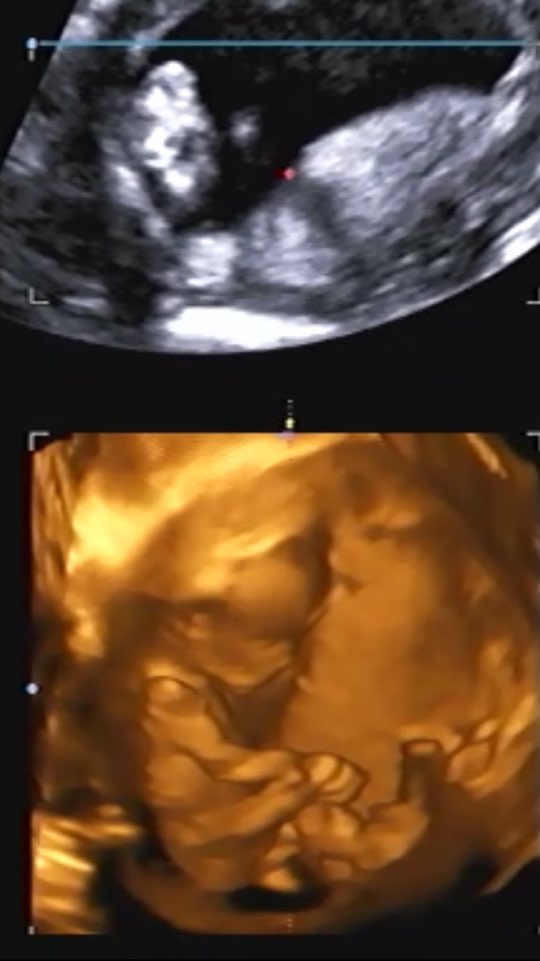

1차 기형아검사 잘 통과했다.

콩이도 모든게 다 정상이고 건강하고, 나도 건강하고....

신기하기 그지 없네...내 뱃속에 저렇게 소중한 생명체가 살고 있다니...

크기 7.1cm

심장박동수 160bpm

목투명대 1.47cm

콧대도 있음 ㅋㅋㅋㅋ

딱 다 정상!!!